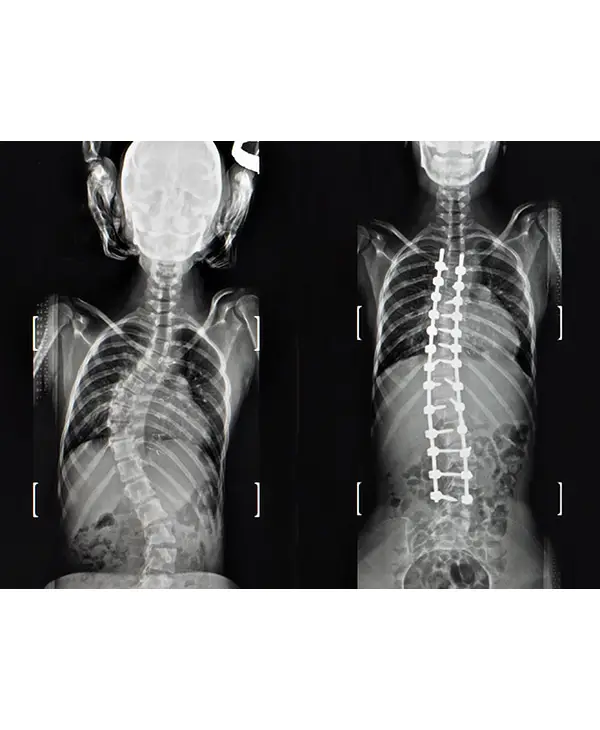

12 year old child with cosmetically and functionally disabling deformity in the back

Diagnosis: Congenital scoliosis with hemivertebra and unsegmented bar

Treatment: Deformity correction with vertebral column resection(VCR) and cage reconstruction

Outcome: child returned to normal life with good self-esteem